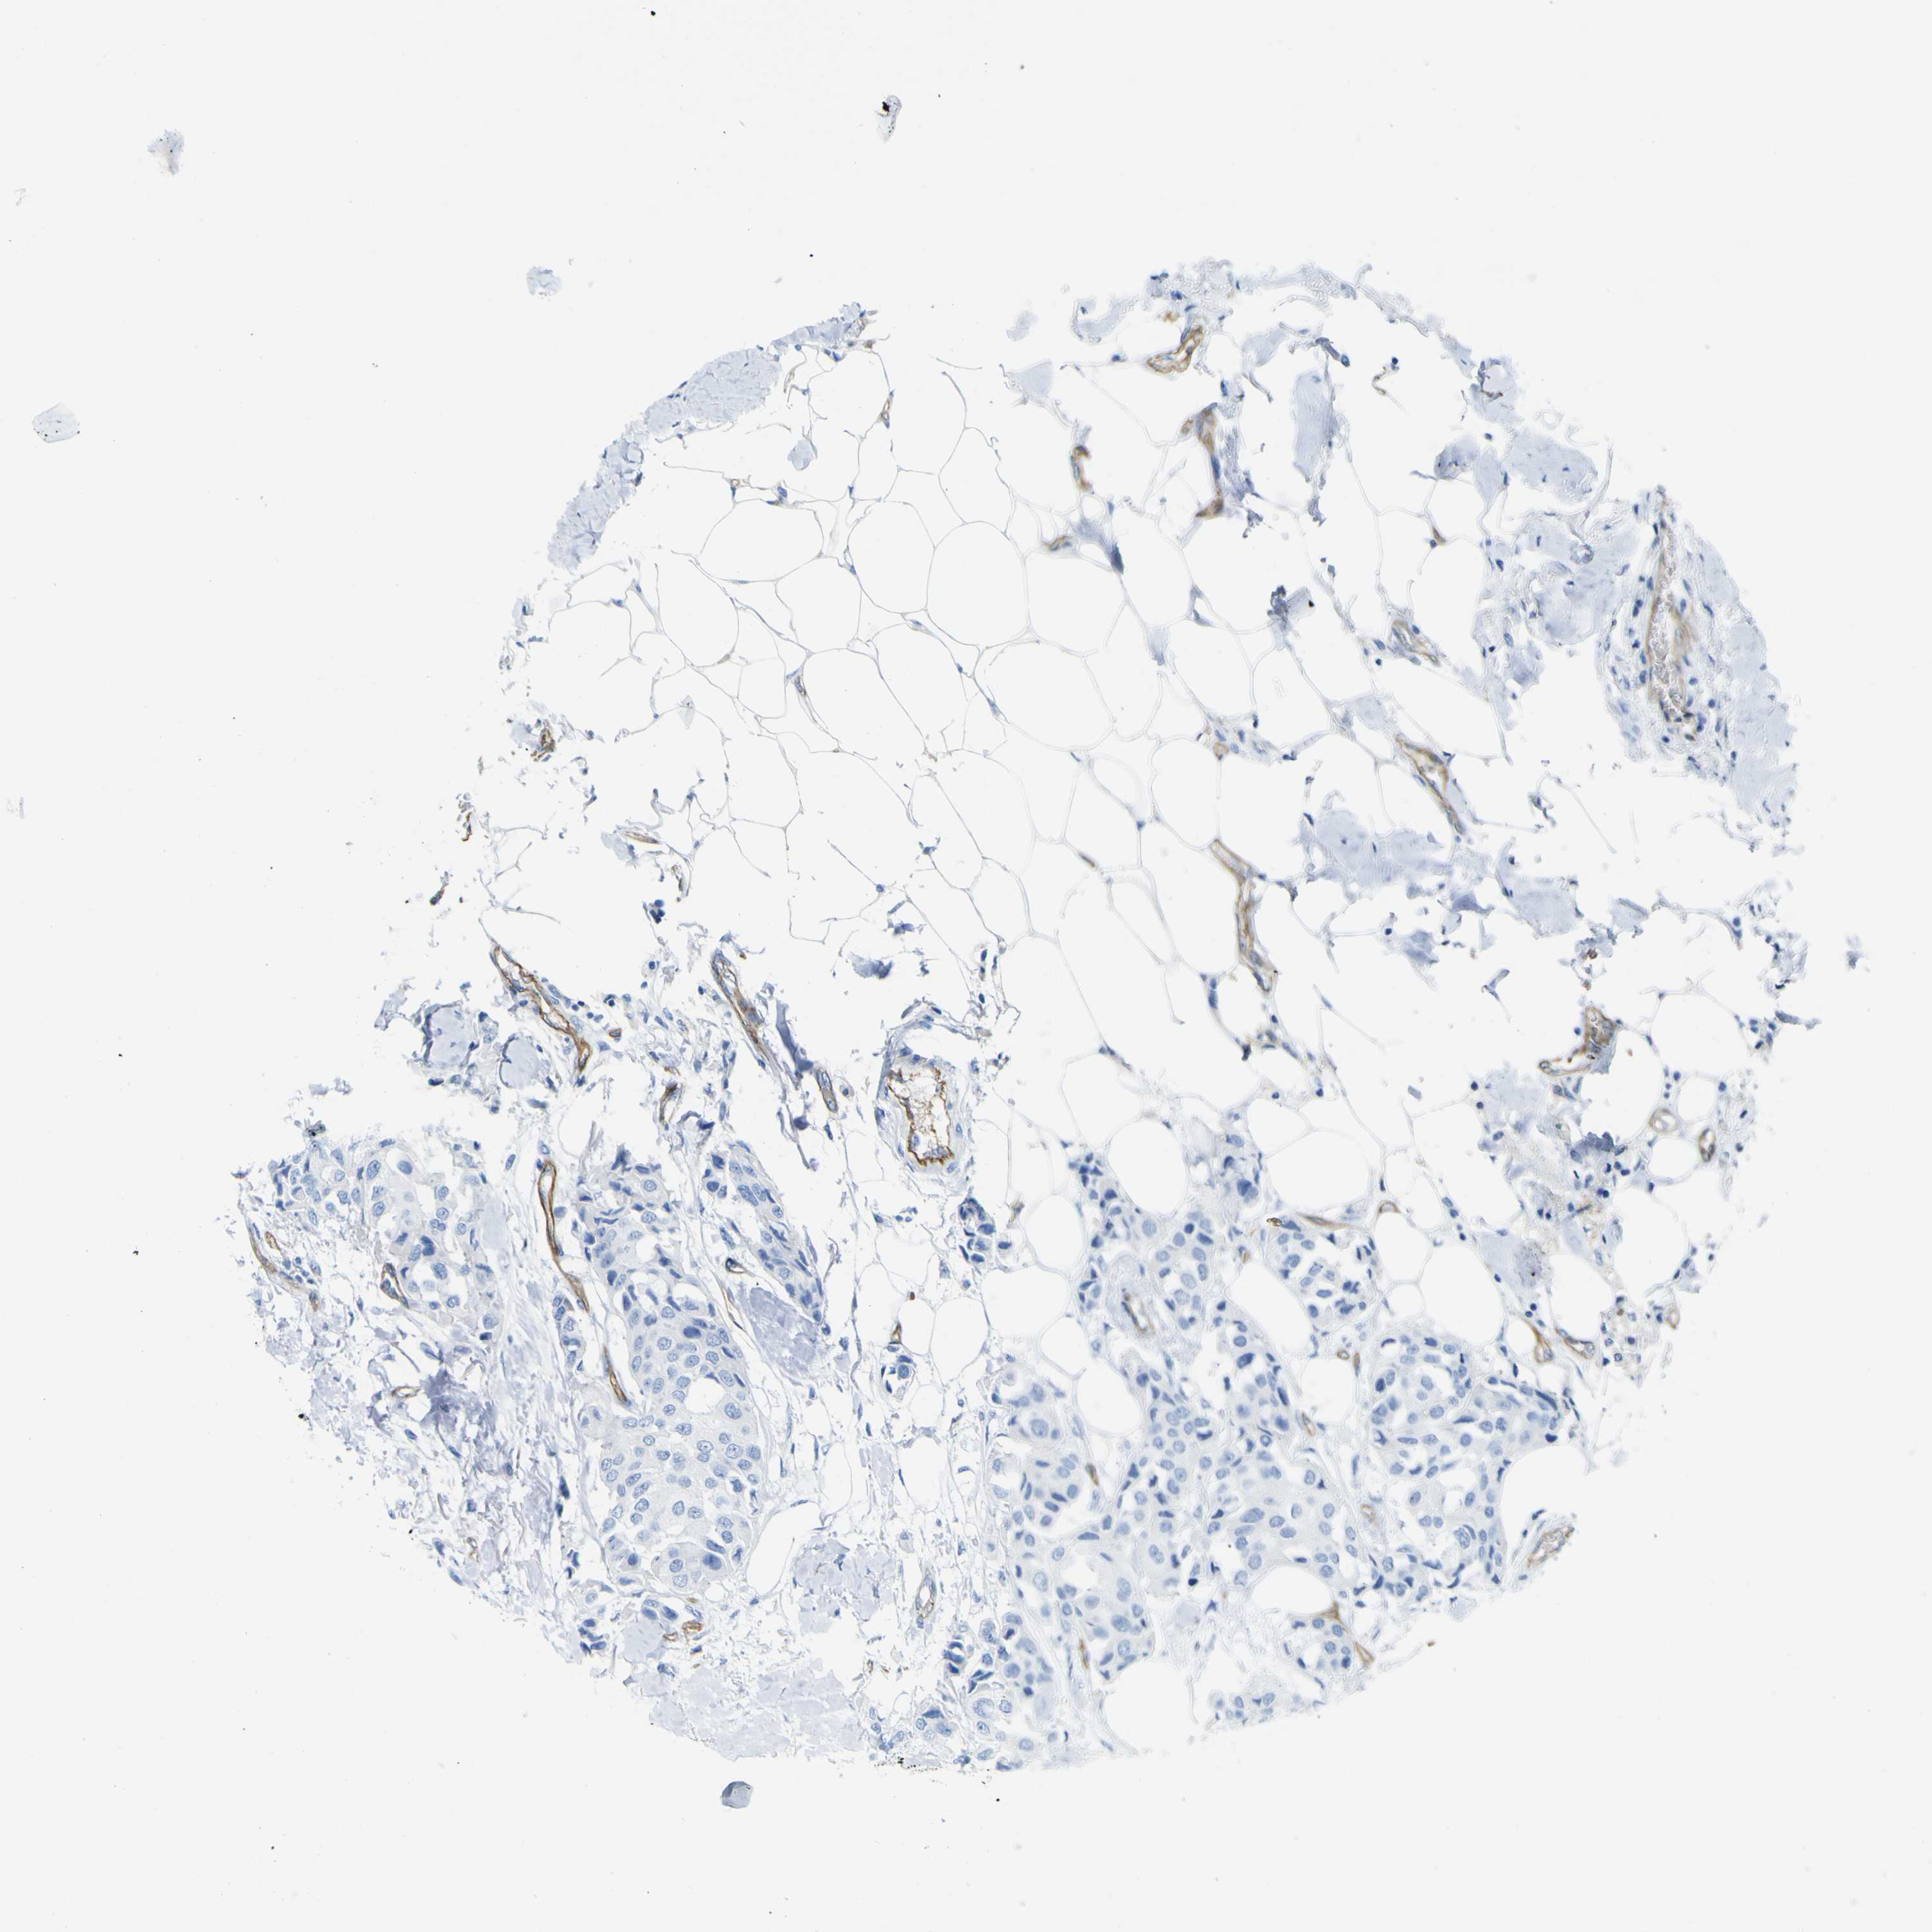

CANCER BREAST CANCER Show tissue menu

BRCA TCGA BRCA VALIDATION PROTEIN EXPRESSION

ANTIBODIES

AND

VALIDATION